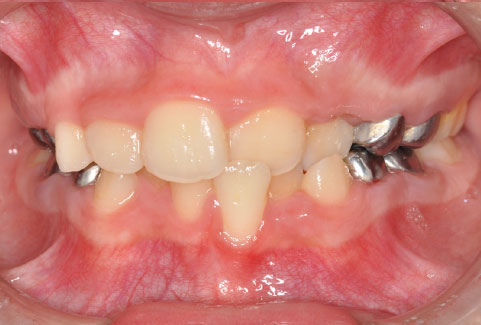

La mordida cruzada es una forma de maloclusión, es decir, un encaje dental inadecuado. Se produce cuando, al morder, algunos dientes superiores quedan por dentro de los inferiores, cuando lo normal sería justo lo contrario: la boca es como una caja de zapatos (los dientes de abajo son la caja y los de arriba la tapa). Puede afectar solo a un lado de la boca (unilateral) o a ambos (bilateral), y se observa tanto en los dientes anteriores como en los molares posteriores.

- Al cerrar la boca, hay dientes superiores claramente por dentro de los inferiores.